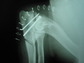

¿QUE ES LA DISPLASIA DE CODO?

La displasia de codo (DC) es una enfermedad hereditaria del desarrollo de las codos, es decir, los animales nacen con codos normales y a medida que crecen, se va desarrollando la DC. Al igual que la Displasia de cadera, se trata de una patología poligénica (inducida por varios genes, no por uno sólo, por eso es tan difícil de erradicar).

Afecta generalmente a perros de razas grandes ( Labrador, Golden Retriever, Pastor Alemán, Boyero de Berna, Terranova,